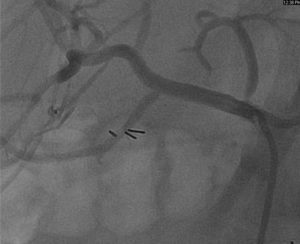

A 55-year-old gentleman with a history of coronary artery disease, diabetes and mesenteric ischemia status post celiac trunk stent placement presented to clinic with abdominal pain. Initially improved in the months following stent placement, now (almost two years later) he is complaining of postprandial left upper quadrant pain, vomiting and a fear of eating. He was scheduled for elective angiography, which revealed a 90{8ceaa46882e4d49283ff23b35262537230ad541262f55a031ead545e66522058} in-stent restenosis in the celiac trunk (Fig 1).